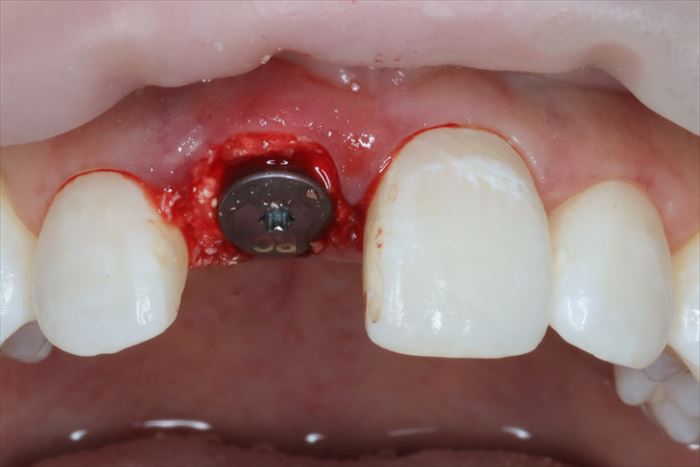

残っていた歯根を抜歯し、顕微鏡下で抜歯窩内部の掻爬を終えました。

心配していた唇側の骨は無事に保存できました。

ヒーリングキャップを締結しました。

歯根の方がインプラントよりも太いため隙間が生じます。

わずかな隙間は血液が貯留して骨となることが判っていますが、念のため骨移植材を準備します。